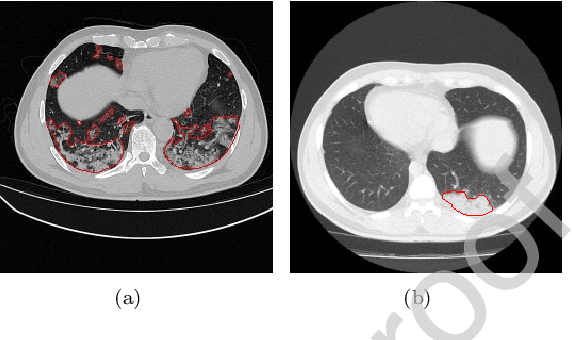

Abstract:Due to the irregular shapes,various sizes and indistinguishable boundaries between the normal and infected tissues, it is still a challenging task to accurately segment the infected lesions of COVID-19 on CT images. In this paper, a novel segmentation scheme is proposed for the infections of COVID-19 by enhancing supervised information and fusing multi-scale feature maps of different levels based on the encoder-decoder architecture. To this end, a deep collaborative supervision (Co-supervision) scheme is proposed to guide the network learning the features of edges and semantics. More specifically, an Edge Supervised Module (ESM) is firstly designed to highlight low-level boundary features by incorporating the edge supervised information into the initial stage of down-sampling. Meanwhile, an Auxiliary Semantic Supervised Module (ASSM) is proposed to strengthen high-level semantic information by integrating mask supervised information into the later stage. Then an Attention Fusion Module (AFM) is developed to fuse multiple scale feature maps of different levels by using an attention mechanism to reduce the semantic gaps between high-level and low-level feature maps. Finally, the effectiveness of the proposed scheme is demonstrated on four various COVID-19 CT datasets. The results show that the proposed three modules are all promising. Based on the baseline (ResUnet), using ESM, ASSM, or AFM alone can respectively increase Dice metric by 1.12\%, 1.95\%,1.63\% in our dataset, while the integration by incorporating three models together can rise 3.97\%. Compared with the existing approaches in various datasets, the proposed method can obtain better segmentation performance in some main metrics, and can achieve the best generalization and comprehensive performance.